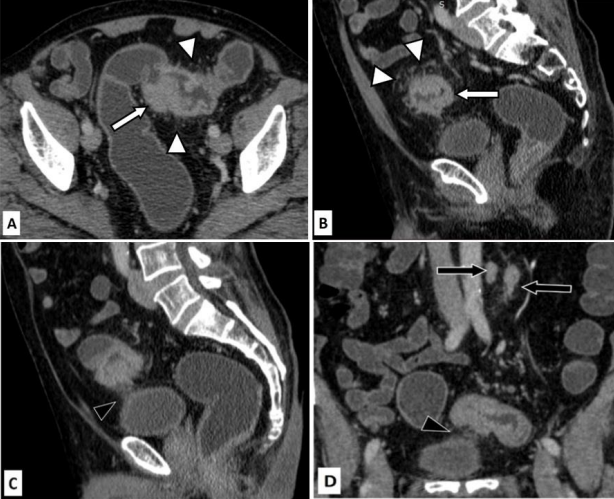

Figure 4: False negative for T4 disease and true positive for nodal negative disease (N0).

Case of 70 years old female with abdominal pain and loss of appetite. She underwent an ultrasoud which showed rectal wall thickening. Colonoscopy was done subsequently which revealed ulcerative growth in the recto-sigmoid junction. Biopsy was taken during colonoscopy which came out to be positive for malignancy (adenocarcinoma).

Figure 4A (Sagittal CT image in venous phase) shows severe apple-core type of wall thickening involving the rectum (white arrow). There is only minimal pericolic fat edema. Extramural vascular invasion is seen (black arrow). The fat planes with urinary bladder and seminal vesicles are maintained (black arrowheads)

Figure 4B (axial CT image in venous phase) shows severe apple-core type of wall thickening (arrow). Figure 4C (Coronal CT image in venous phase) shows the thickening with only minimal pericolic fat stranding (arrow). Figure 4D (Axial CT image in venous phase) shows multiple dilated small bowel loops with air-fluid levels suggestive of bowel obstruction. Minimal ascites is present (arrow).